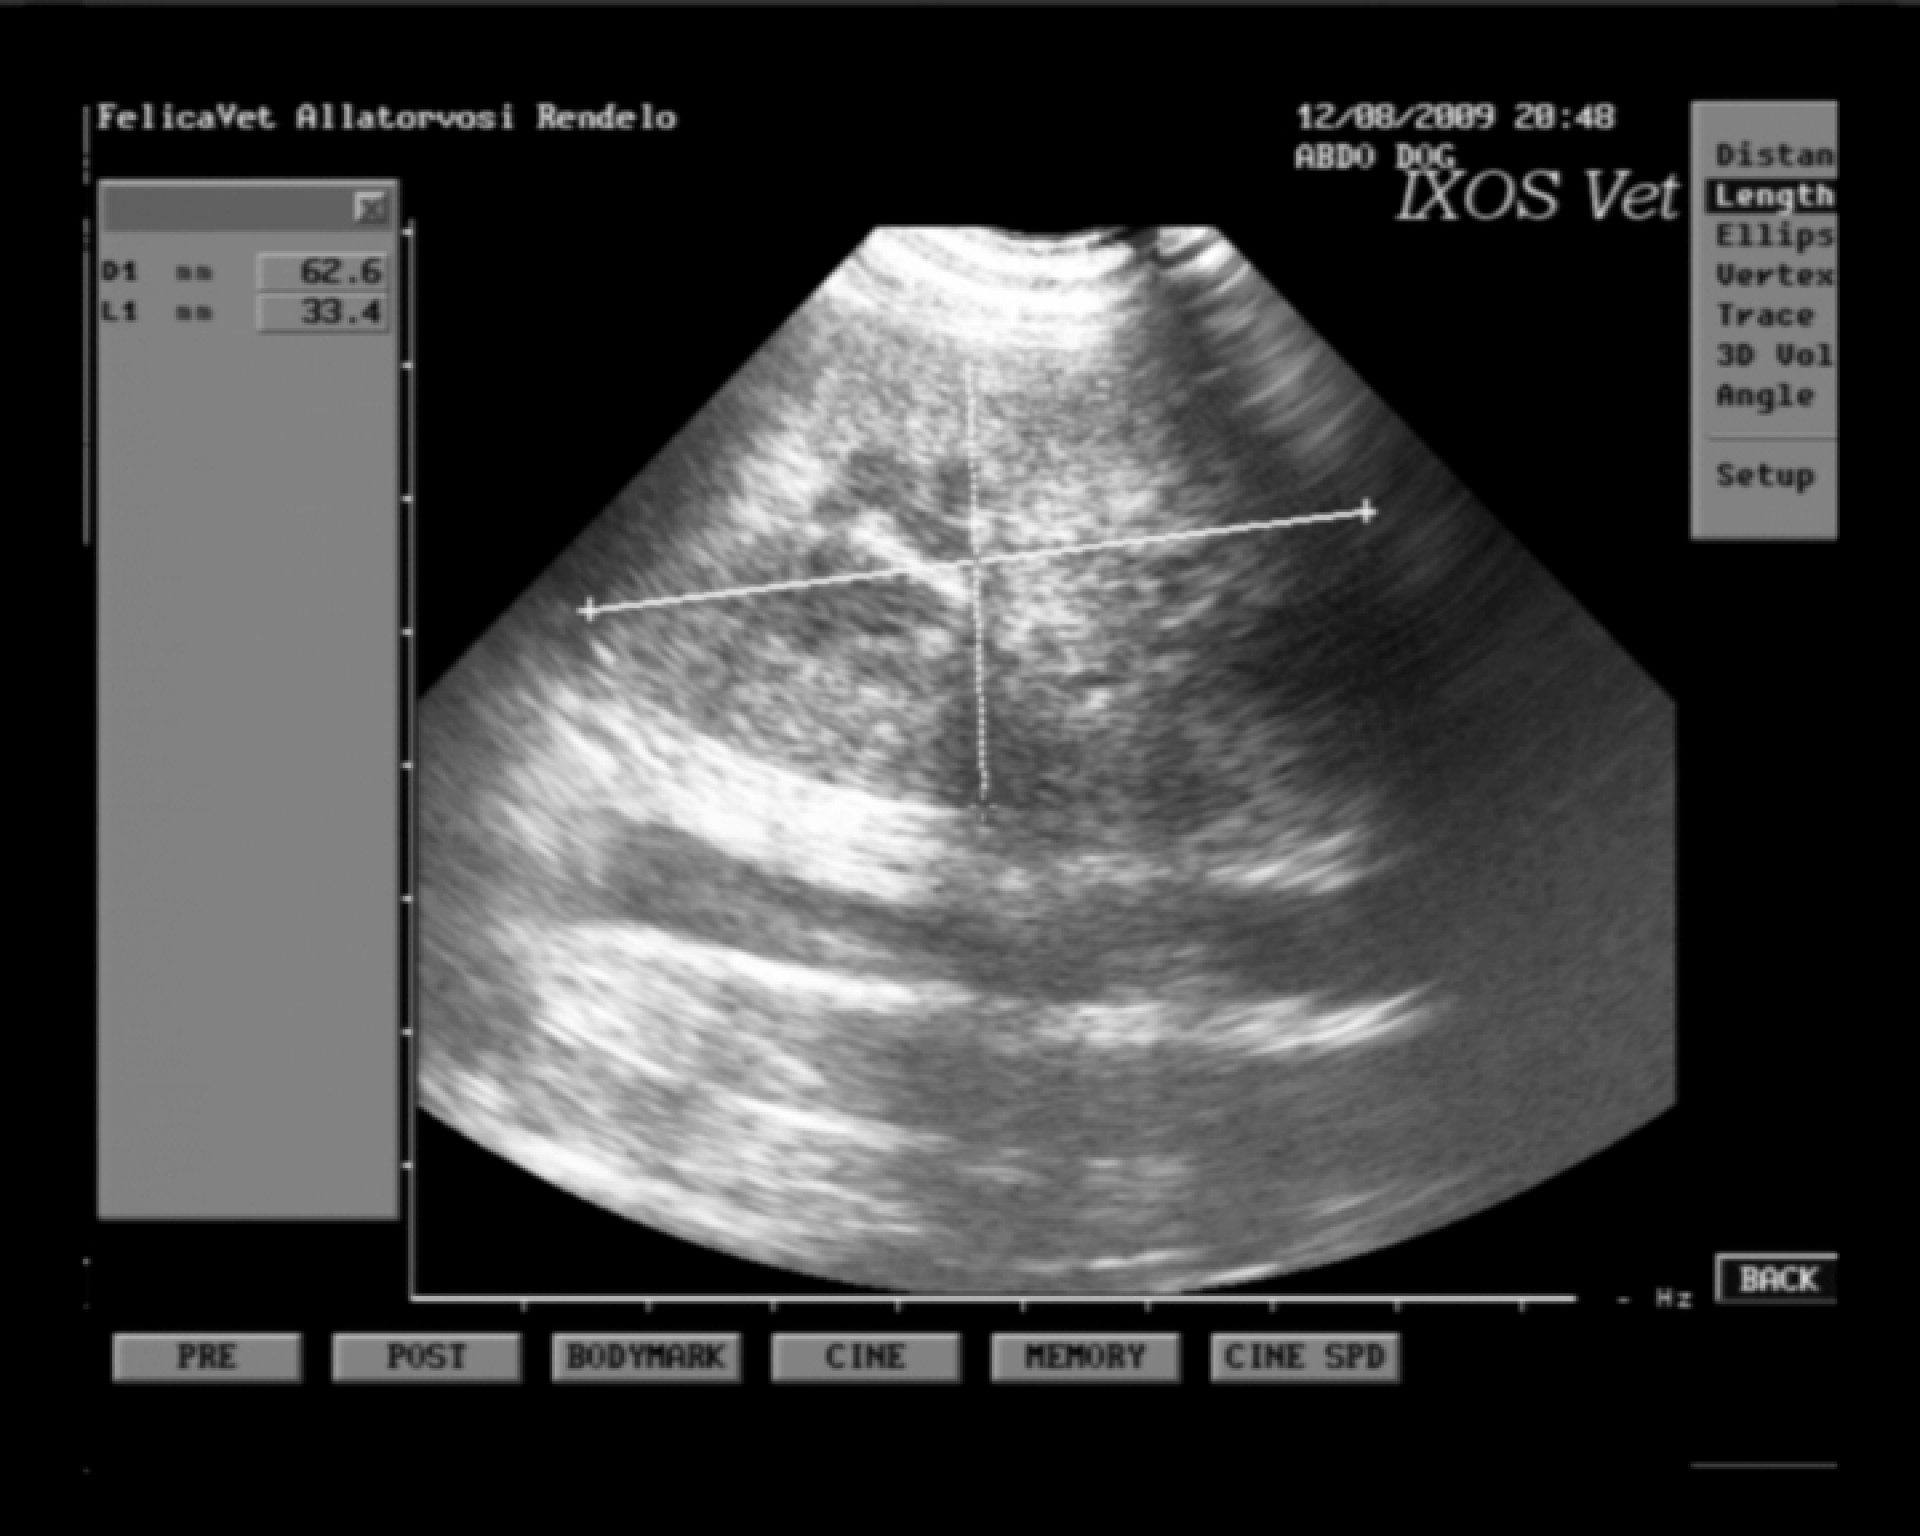

Bár magam nem vagyok az ultrahang diagnosztikában különösebben jártas, a hasüreg vizsgálata során vizelettel telt hólyagot, normális szerkezetű veséket és egy jelentősen megnagyobbodott lépet találtam.

A lép Doppler vizsgálatával a szerv vérkeringésének teljes hiánya volt igazolható.

A diagnózis: lépcsavarodás. Meglehetősen ritka kórkép, mely a kórelőzménnyel és a klinikai tünetekkel teljesen összevág.